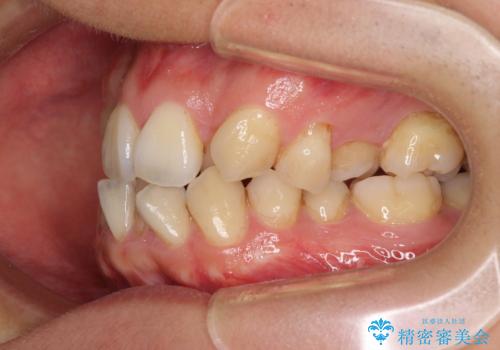

上顎の左右側切歯(前から2番目)が裏側に隠れいてる状態で、咬み合わせや清掃性に大きな問題が認められました。

叢生が著しいため、上下左右の小臼歯4本を抜去し、目立たないワイヤー装置にて矯正治療を行うこととしました。

下顎の歯列全体が右側にずれているため、右下のみ第二小臼歯を抜歯し、上顎は補助装置を使用して、極力上下の正中を合う位置にて咬み合わせを改善するようにしました。